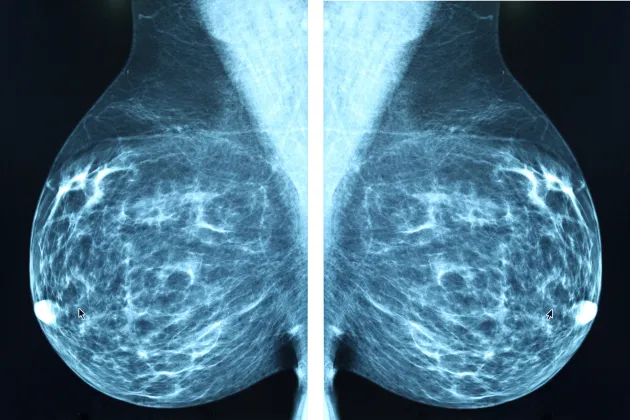

Vid Lunds universitet bedrivs olika typer av cancerforskning. Forskningen har som mål att förbättra diagnoser, prognoser, behandling och vård inom cancer. De vanligaste cancerformerna i Sverige är bröstcancer, prostatacancer, och tarmcancer.

- använder bildåtergivning och strålbehandling för att förbättra verktygen inom grundforskning, behandling och diagnostik

Artificiell intelligens (AI) och maskininlärning skapar nya möjligheter att analysera exempelvis bilder inom mikroskopi eller medicinsk diagnostik. Denna kunskap banar väg för nya upptäckter och användningsområden.

Fickultraljud – ett ultraljud som får plats i fickan är ett exempel på en sådan innovation. Det är en smarttelefon och algoritm kopplad till tusentals kliniska bröstbilder som ger diagnostik där den bäst behövs.